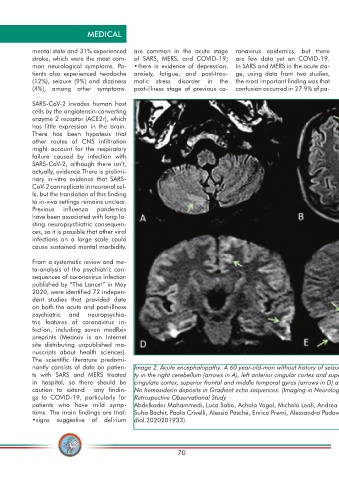

nantly consists of data on patien- Image 2. Acute encephalopathy. A 60 year-old-man without history of seizures presenting with convulsion. (A-B) Multifocal areas of FLAIR hyperintensi-

ts with SARS and MERS treated ty in the right cerebellum (arrows in A), left anterior cingular cortex and superior frontal gyrus (arrows in B). (C-D) Restricted diffusion in the left anterior

in hospital, so there should be cingulate cortex, superior frontal and middle temporal gyrus (arrows in D) and right cerebellum (arrows in E), consistent with cerebellar diaschisis. F)

caution to extend any fi ndin- No hemosiderin deposits in Gradient echo sequences. (Imaging in Neurological Disease of Hospitalized COVID-19 Patients: An Italian Multicenter

gs to COVID-19, particularly for Retrospective Observational Study

patients who have mild symp- Abdelkader Mahammedi, Luca Saba, Achala Vagal, Michela Leali, Andrea Rossi, Mary Gaskill, Soma Sengupta, Bin Zhang, Alessandro Carriero,

toms. The main fi ndings are that: Suha Bachir, Paola Crivelli, Alessio Paschè, Enrico Premi, Alessandro Padovani, and Roberto Gasparotti https://pubs.rsna.org/doi/10.1148/ra-

•signs suggestive of delirium diol.2020201933)